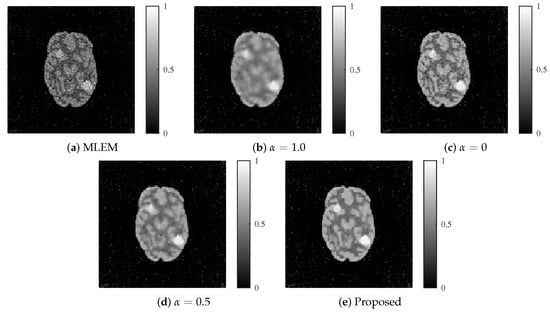

Figure 11.

Reconstructed images for each method using clinical data: (a) MLEM, (b) MLEM with L1 regularization (), (c) MLEM with L2 regularization (), (d) MLEM with ElasticNet regularization ( fixed), and (e) proposed dynamic ElasticNet regularization. The proposed method also achieved superior performance in clinical images.

The MLEM method generated noisy images compared with the other methods, rendering it unsuitable for observing images. Although the regularization with the L1 and L2 aided in noise reduction, the images contained more noise than those generated using the proposed method, failing to provide adequate noise suppression. Similar to the numerical phantom experiment, the proposed method outperformed the others the most in terms of noise and resolution.

The results obtained from the clinical data are shown in Figure 11. The parameters utilized in Equations (9) and (11) were and .